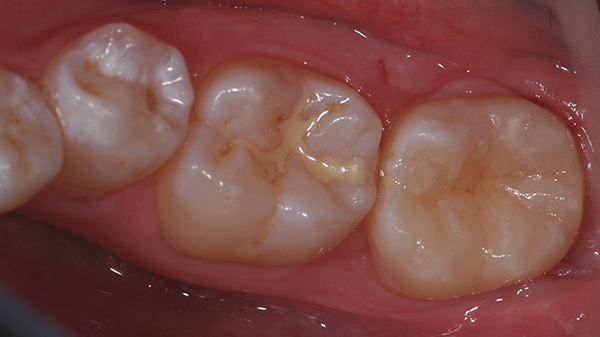

Sono seguiti i procedimenti di rifinitura, controllo occlusale dei contatti e quindi la dimissione della paziente.

Si è rivista la paziente una settimana dopo i procedimenti di cementazione per un controllo e per verificare la fedeltà delle scelte cromatiche stabilite che, inevitabilmente, apparivano alterate dopo la rimozione della diga a causa della disidratazione dello smalto periferico e dei denti contigui.